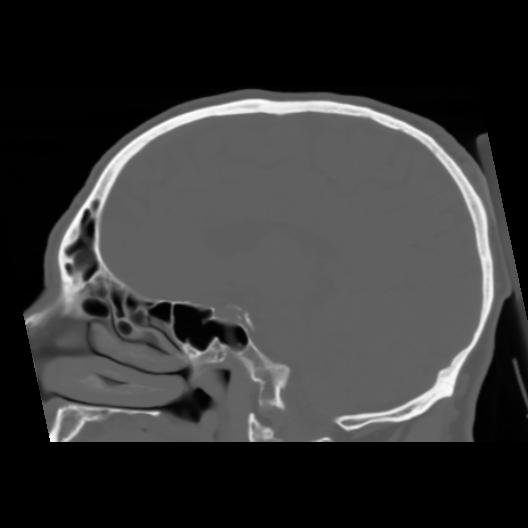

6 CEREBRO,,Sagittal,3.000,CEREBRO,Sagittal,